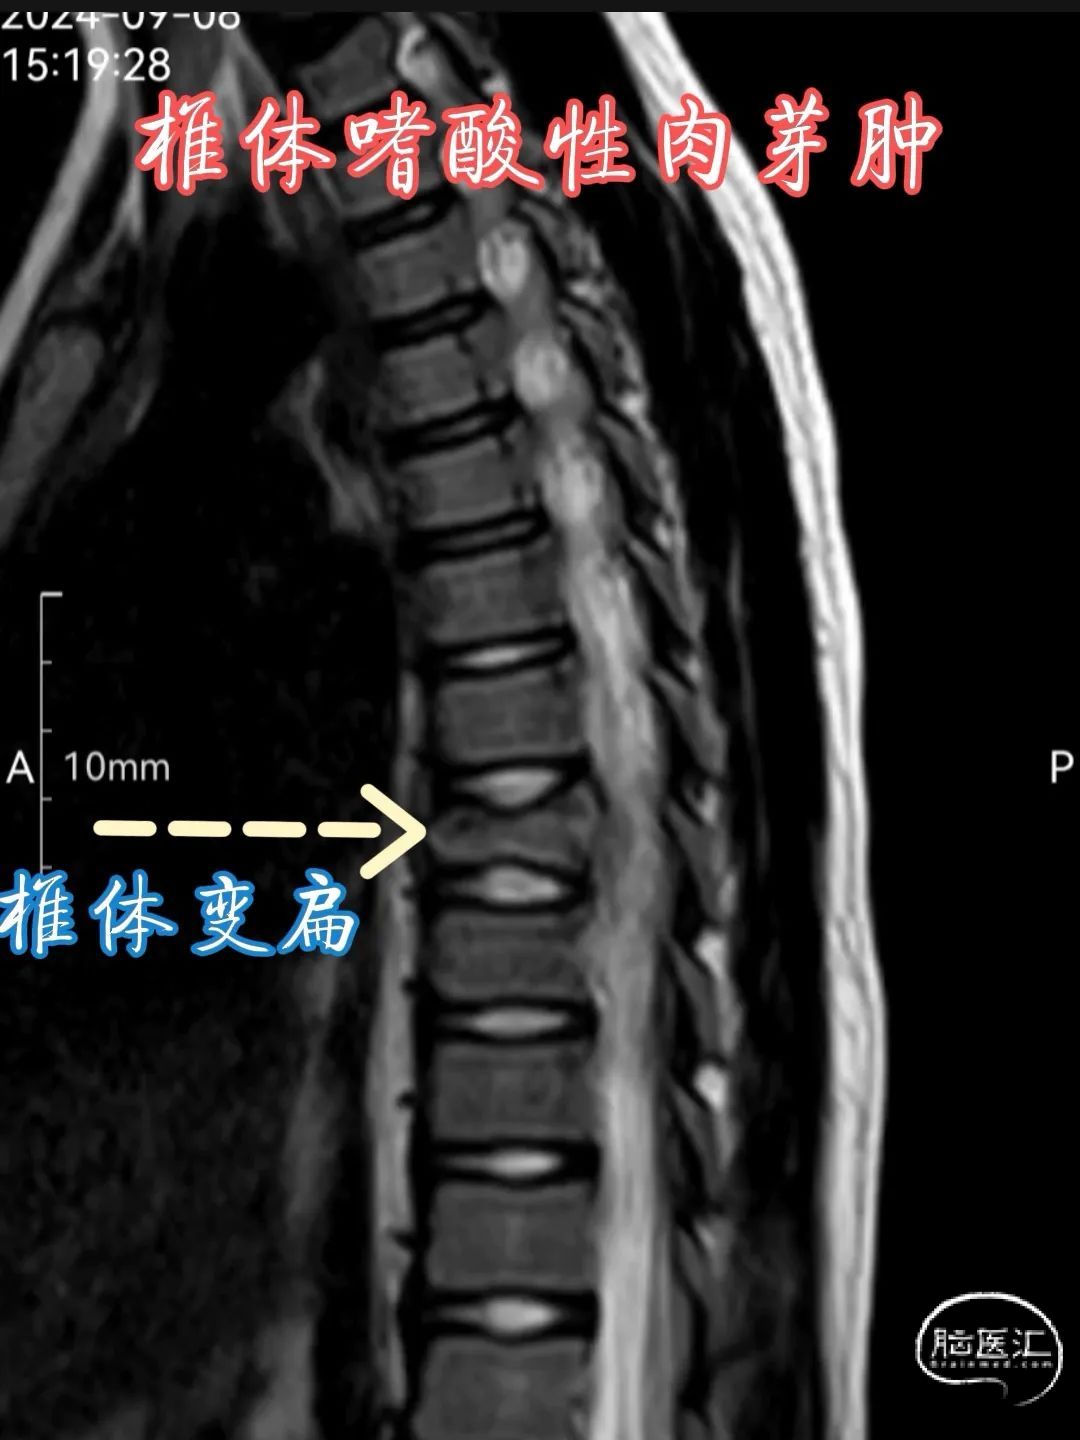

•MRI 检查 :MRI 对于检测椎体嗜酸性肉芽肿具有较高的敏感性,能够清晰地显示病变的范围、部位、形态以及与周围组织的关系。在 T1 加权像上,病变通常呈低到中等信号强度,与正常骨髓相比信号较低;在 T2 加权像上则呈高信号强度,这是由于病变组织内含有较多的水分和黏多糖等成分。此外,MRI 还可显示病变周围的软组织水肿、炎症反应以及神经受压等情况,对于判断病情和制定治疗计划具有重要价值。